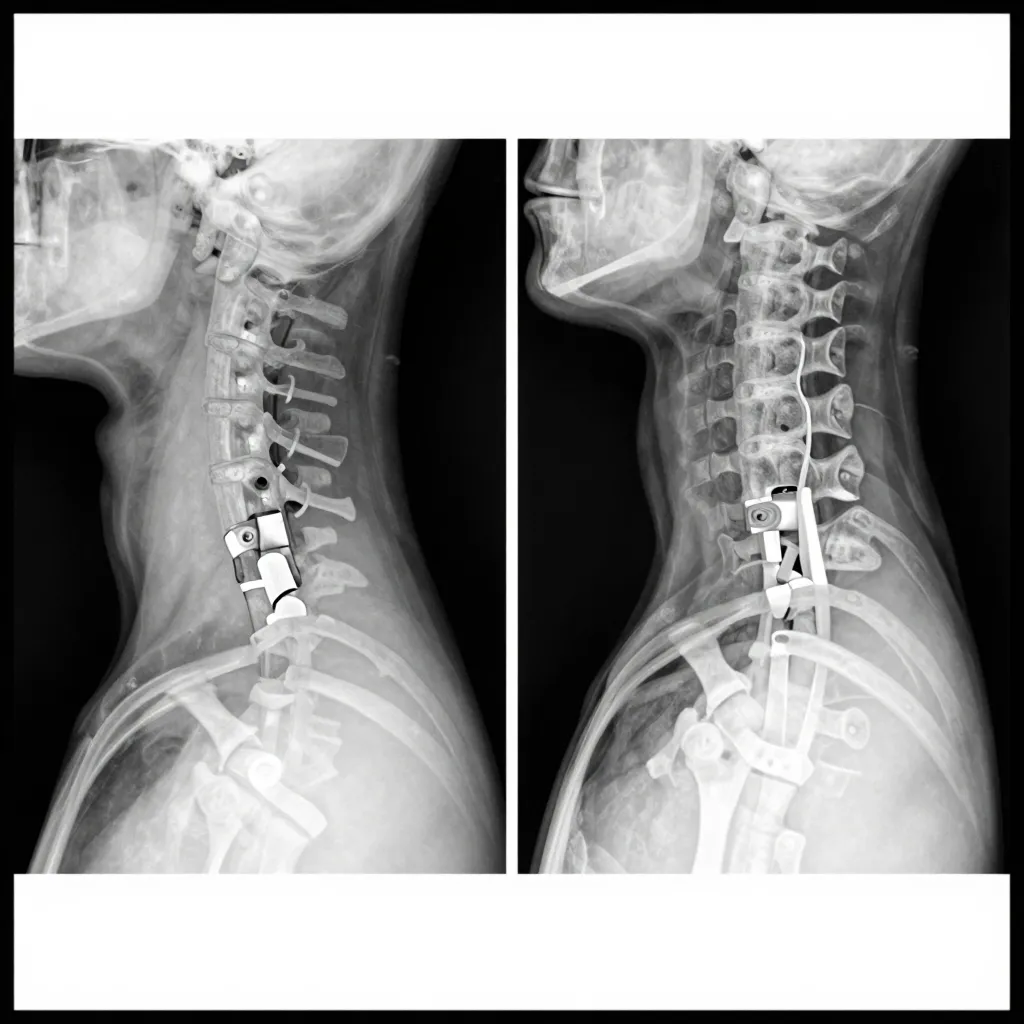

Delhi Sciatica Surgery Due to three fractures in the D9 and D10 vertebrae, a cirugía de columna vertebral was performed...